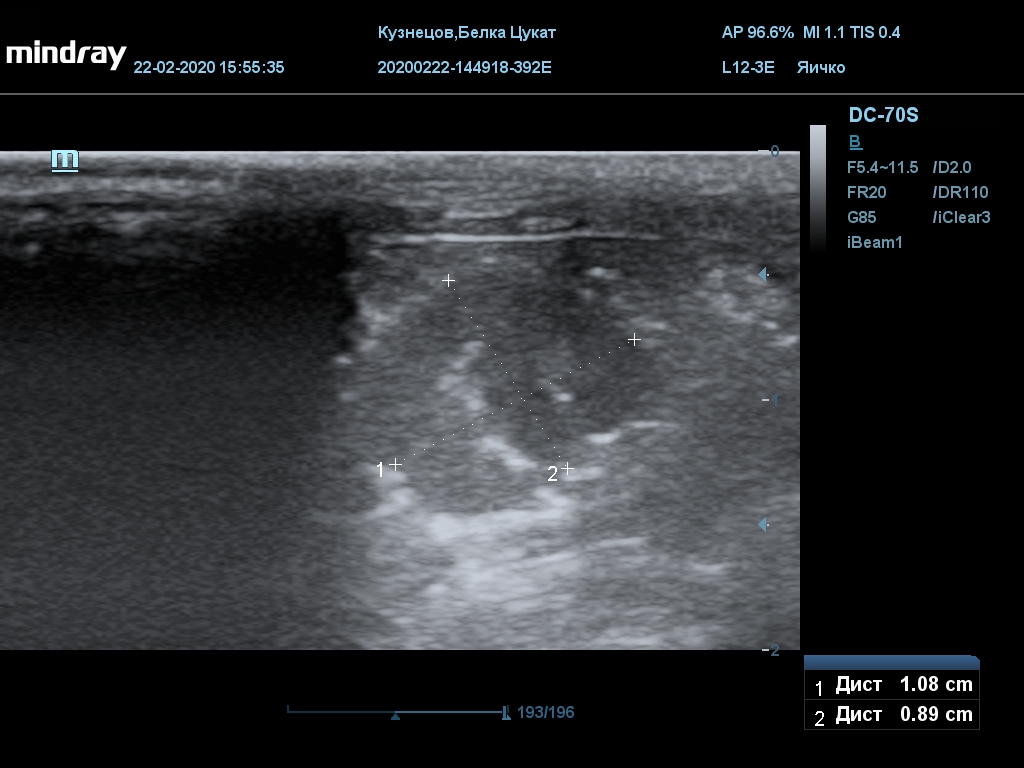

УЗИ

(почки, мочевой пузырь и, предположительно, простата)

Обращаю внимание, что делала УЗИ и писала заключение узист, которая специализируется на кошках и собаках, поэтому она сделала узи и описала, как смогла, но тонкостей грызунячьей анатомии она не знает.

Приложил только фото, есть ещё пара видео, но не знаю, как тут выложить, и надо ли.

Почка левая ровная, размер 12 х 7,6 х 8,2 мм. Контур ровный чёткий. КМД отсутствует, лоханка расширена незначительно, объёмных включений не выявлено.

Почка правая ровная, контур чёткий, размер 13,5 х 8,7 х 9,3 мм. Капсула визуализируется. КМД отсутствует, лоханка не расширена. Объёмные образования не выявлены.

Заключение: УЗпризнаки уролитиаза, объёмная структура каудальнее мочевого пузыря. Признаки расширения левой лоханки.

УЗИ

(почки, мочевой пузырь и, предположительно, простата)

Обращаю внимание, что делала УЗИ и писала заключение узист, которая специализируется на кошках и собаках, поэтому она сделала узи и описала, как смогла, но тонкостей грызунячьей анатомии она не знает.

Почка левая ровная, размер 12 х 7,6 х 8,2 мм. Контур ровный чёткий. КМД отсутствует, лоханка расширена незначительно, объёмных включений не выявлено.

Почка правая ровная, контур чёткий, размер 13,5 х 8,7 х 9,3 мм. Капсула визуализируется. КМД отсутствует, лоханка не расширена. Объёмные образования не выявлены.

Заключение: УЗпризнаки уролитиаза, объёмная структура каудальнее мочевого пузыря. Признаки расширения левой лоханки.